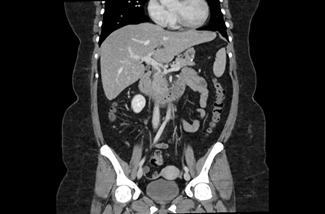

The initial physical examination showed a patient in discomfort but with normal vital signs. The abdominal palpation revealed epigastric tenderness without guarding or without other signs suggestive of acute abdomen. Surgical sites appeared to be well-healed, clean, and dry with no evidence of drainage or dehiscence. The laboratory analyses showed elevated inflammatory parameters (13,500 leukocytes and a C-reactive protein level of 123,20 mg/dL) and normal levels of amylase and lipase. A contrast-enhanced abdominopelvic computed tomography (CT) scan (Figures 1, 2, and 3) showed a dilatation in the mesenteric vessels, particularly the superior mesenteric vein, which had a luminal filling defect near its confluence with the splenic vein. The CT scan also revealed thickening of the adjacent adipose tissue, albeit without signs of intestinal ischemia. The patient was admitted to ward and started on LMWH 100 mg every 12 hours along with reinforced IV hydration. After three days in the hospital, she was discharge home asymptomatic. Anticoagulation therapy was continued with LMWH for one month before transitioning to a non-vitamin K antagonist oral anticoagulant (NOAC), specifically Apixaban 5 mg every 12 hours, and the use of estrogen for birth control was discontinued. At the three-month follow-up, the patient had lost 20 kg and was scheduled to repeat the CT scan and to discontinue anticoagulation therapy approximately six months after the thrombotic event.

The most common presentation of PMVT is nonspecific, often characterized by a diffuse abdominal pain, accompanied by nausea, vomiting, and changes in bowel habits.12 Enhanced abdominal CT with intravenous contrast, is the gold standard method for diagnosing PMVT, boasting a high sensitivity of 90%. (10) In the CT scan, we can identify the affected vascular territory and determine if there is intestinal compromise. The presence of free fluid, pneumoperitoneum, or indirect signs of intestinal ischemia (non-enhancing or hypo-enhancing bowel wall after contrast injection, pneumatosis intestinalis, portomesenteric venous gas and alteration in wall thickness) are warning signs that should prompt urgent surgery.13